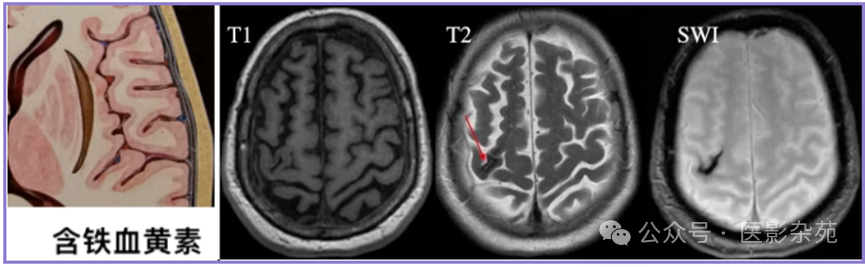

细胞内含铁血黄素

T1:低信号

T2:低信号